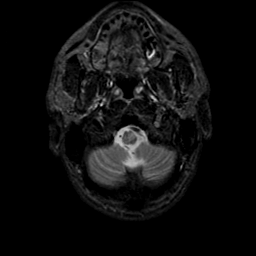

MR Study #9, April 14, 1991 -- Slice #4

[Home][Help][Clinical][Tour 1][Tour 2] Slice 4